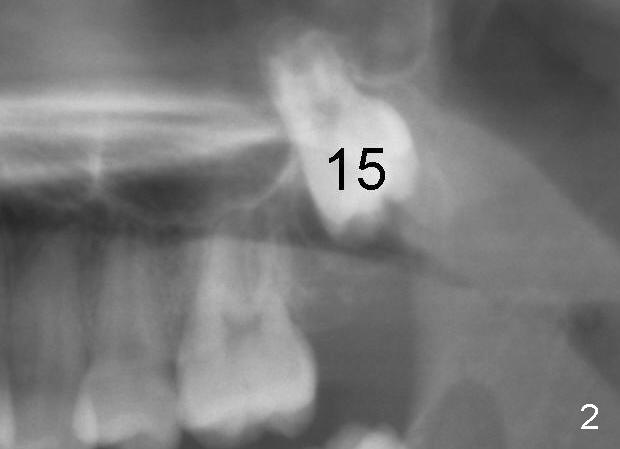

When the female patient was 11 years 2 months (Fig.1) and 12 years 10 months (Fig.2) old, the eruption of #15 is delayed. The tooth is surgically uncovered with bonding an eruption chain 1 month post banding. Three (Fig.3), 4 (Fig.4) and 6 (Fig.5) months post banding, eruption appears to be slow with elastics.